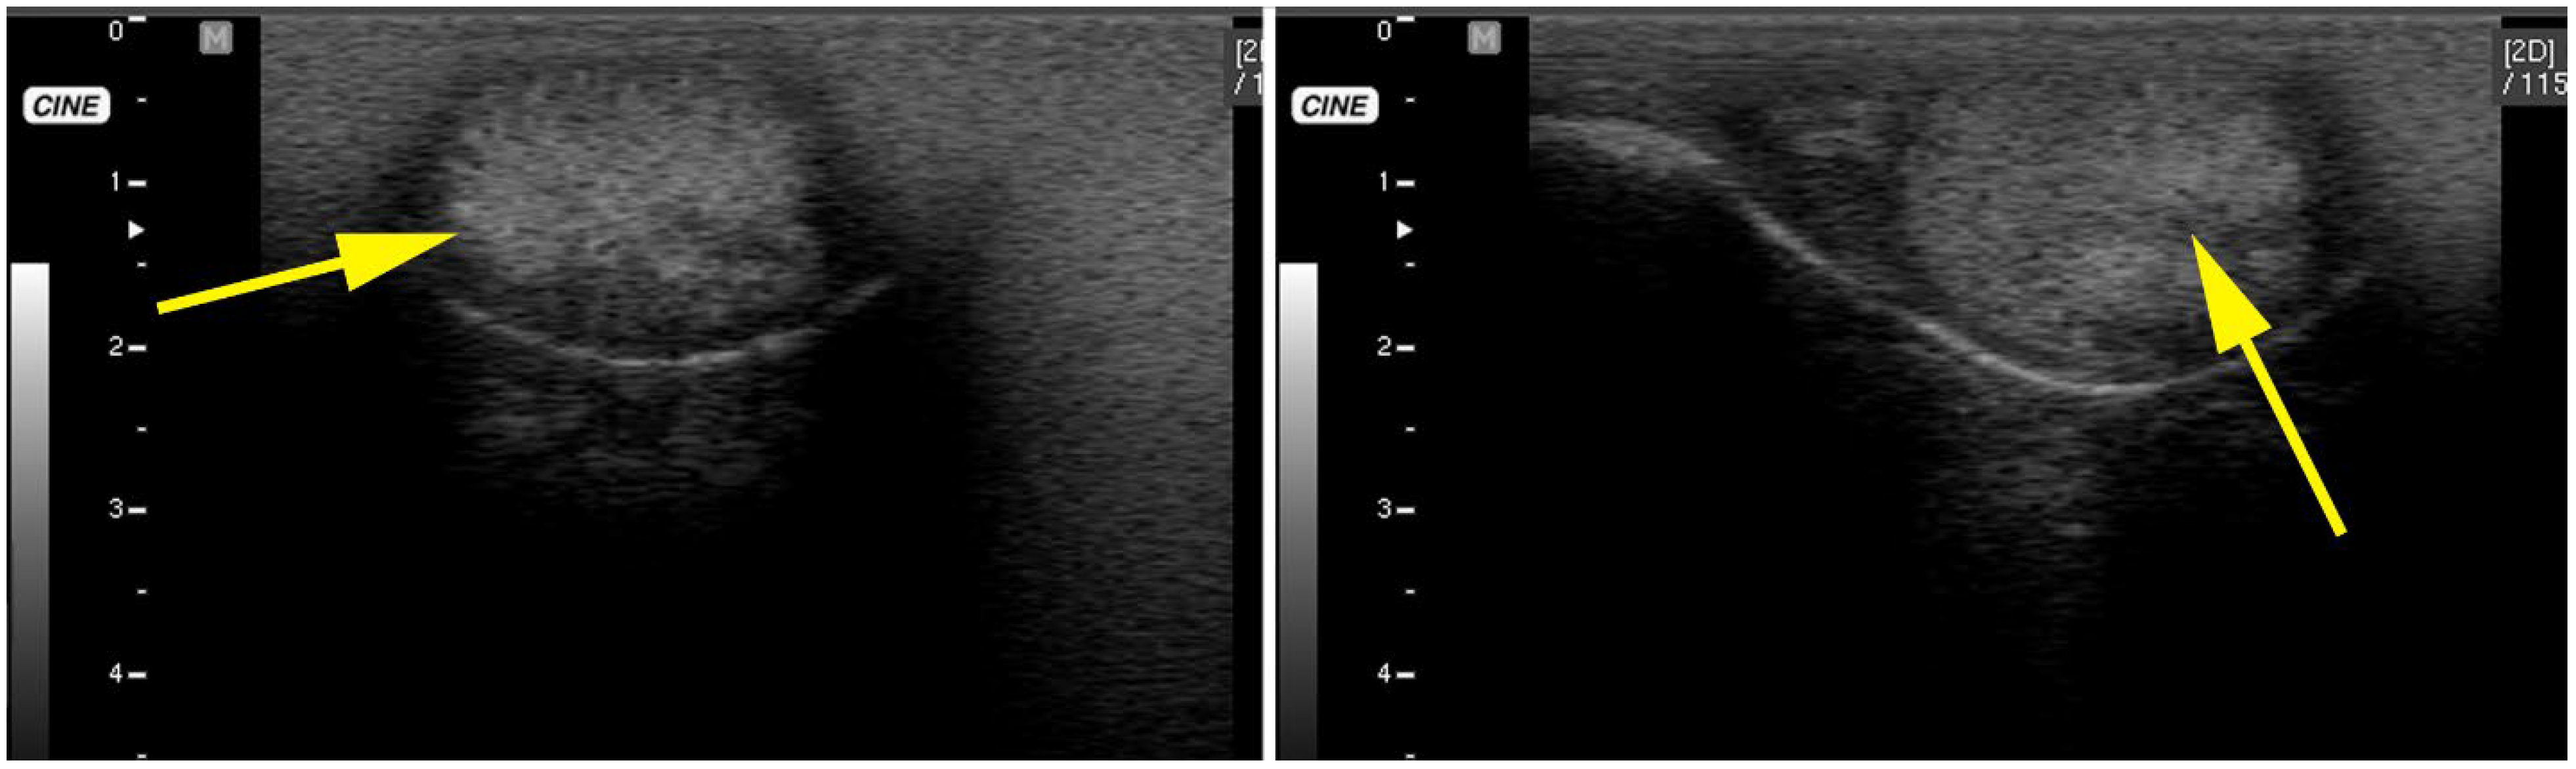

3.3. Testicular and Epididymal Cysts

- Kutzler, M.A.; Shoemaker, M.; Valentine, B.A. Bilateral Cystic Rete Testis in an Alpaca (Lama pacos). J. Vet. Diagn. Investig. 2006, 18, 303–306. [Google Scholar] [CrossRef]

- Gray, G.A.; Dascanio, J.J.; Kasimanickam, R. Bilateral Epididymal Cysts in an Alpaca Male Used for Breeding. Can. Vet. J. 2007, 48, 741–744. [Google Scholar]

- Bott, I.; Pearson, L.K.; Rodriguez, J.S. Prevalence and Pathologic Features of Rete Testis Cysts in Alpacas (Vicugna pacos). Clin. Theriogenol. 2010, 2, 395. [Google Scholar]